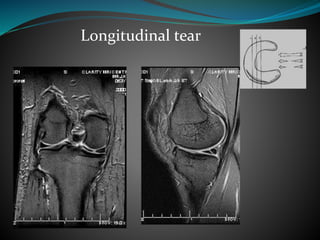

Longitudinal tear

 Bucket Handle Tear- Longitudinal tear

along the length of the meniscus and the

inner rim flips into the intercondylar notch

while remaining attached to the anterior

and posterior horns.

 Double-PCL sign -The flipped fragment

lies inferior and anterior to the PCL